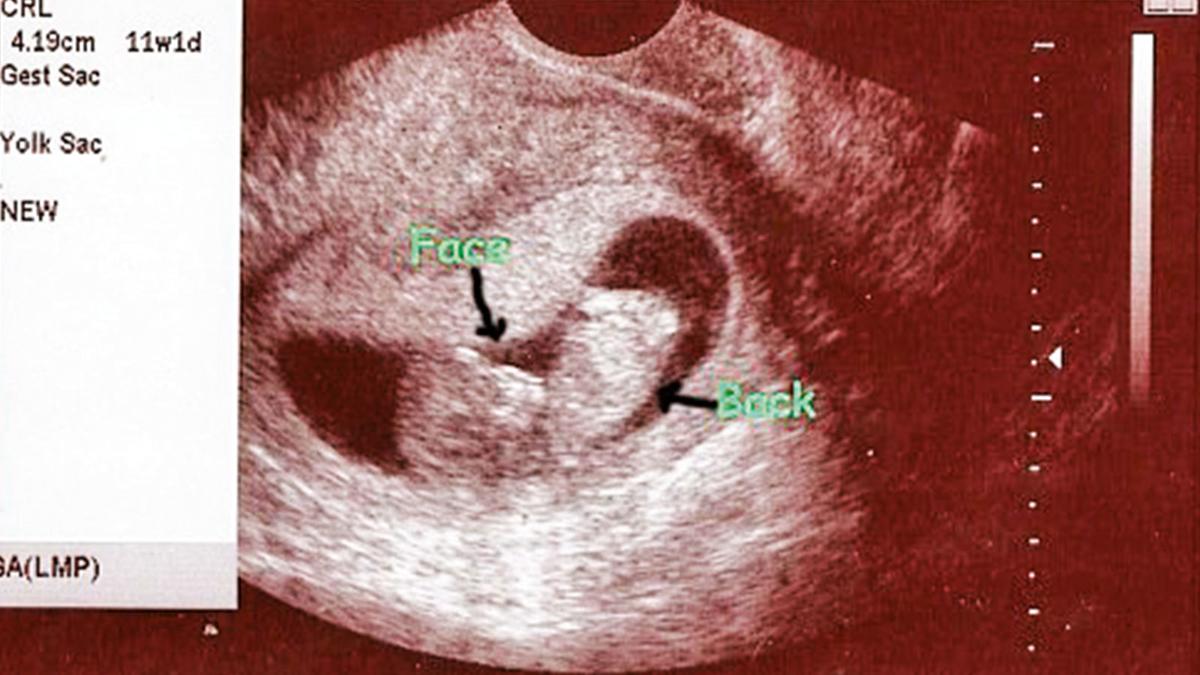

Tıpta 'karaciğer dış gebeliği' olarak adlandırılan, döllenmiş yumurtanın rahim yerine karaciğer dokusuna yerleşmesiyle oluşan nadir bir durum, Peru'da hayata tutundu. Carlos Lanfranco La Hoz Hastanesi'nde sezaryen operasyonla doğum yapan 19 yaşındaki kadının, 3.6 kilo ağırlığında bebeği 40. haftada dünyaya geldi. Bu, Peru'da ilk kez başarıyla sonuçlanan bir karaciğer dış gebelik vakası olurken, dünya genelinde de anne ve bebeğin birlikte hayatta kaldığı dördüncü vaka olarak tarihe geçti.